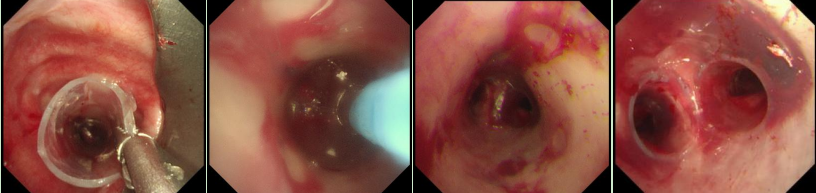

在硬質(zhì)支氣管鏡引導(dǎo)下,手術(shù)團(tuán)隊(duì)首先對(duì)狹窄部位進(jìn)行球囊擴(kuò)張。隨后,將術(shù)前根據(jù)患者三維CT數(shù)據(jù)定制的Y型硅酮支架精準(zhǔn)覆蓋于氣管狹窄段。該支架確保與患者自身的氣道解剖結(jié)構(gòu)完美貼合,實(shí)現(xiàn)最佳支撐效果,并最大限度減少粘膜刺激增生等特點(diǎn)。支架展開后穩(wěn)定支撐于隆突及雙側(cè)主支氣管,氣道狹窄立即得到解除。

隨著手術(shù)順利完成,趙先生蘇醒后自覺呼吸順暢,術(shù)后復(fù)查顯示支架位置良好,氣道通暢,呼吸困難癥狀顯著緩解。